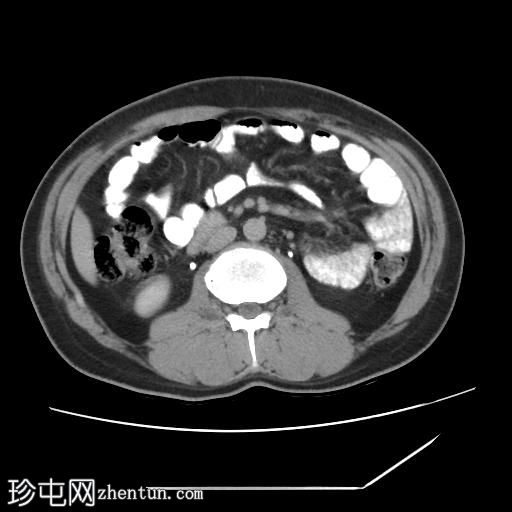

口服造影剂

CT扫描显示胰腺组织完全包绕十二指肠第二段。未发现胰周结节或肿块。

左肝III段可见一低密度囊肿,直径约15 mm。